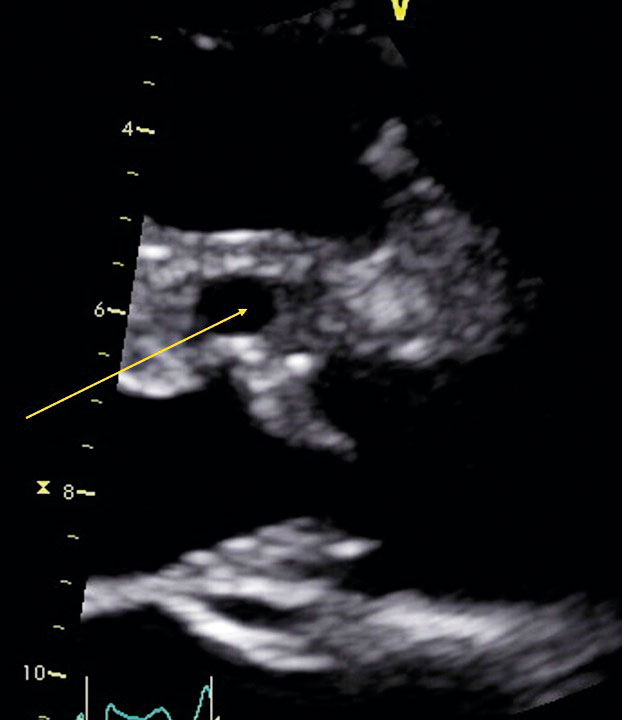

Transesofagal fyrrumsvy: vegetation på trikuspidalisklaffen.

Transesofagal kortaxelvy: vegetation på trikuspidalisklaffen.